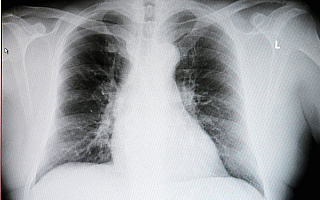

Rzadkie choroby układu oddechowego – jak je wykryć? Specjalne szkolenie przeprowadzili pulmonolodzy z całego kraju

Lekarze pierwszego kontaktu z całego województwa szkolili się w wykrywaniu rzadkich chorób układu oddechowego. Konferencję…